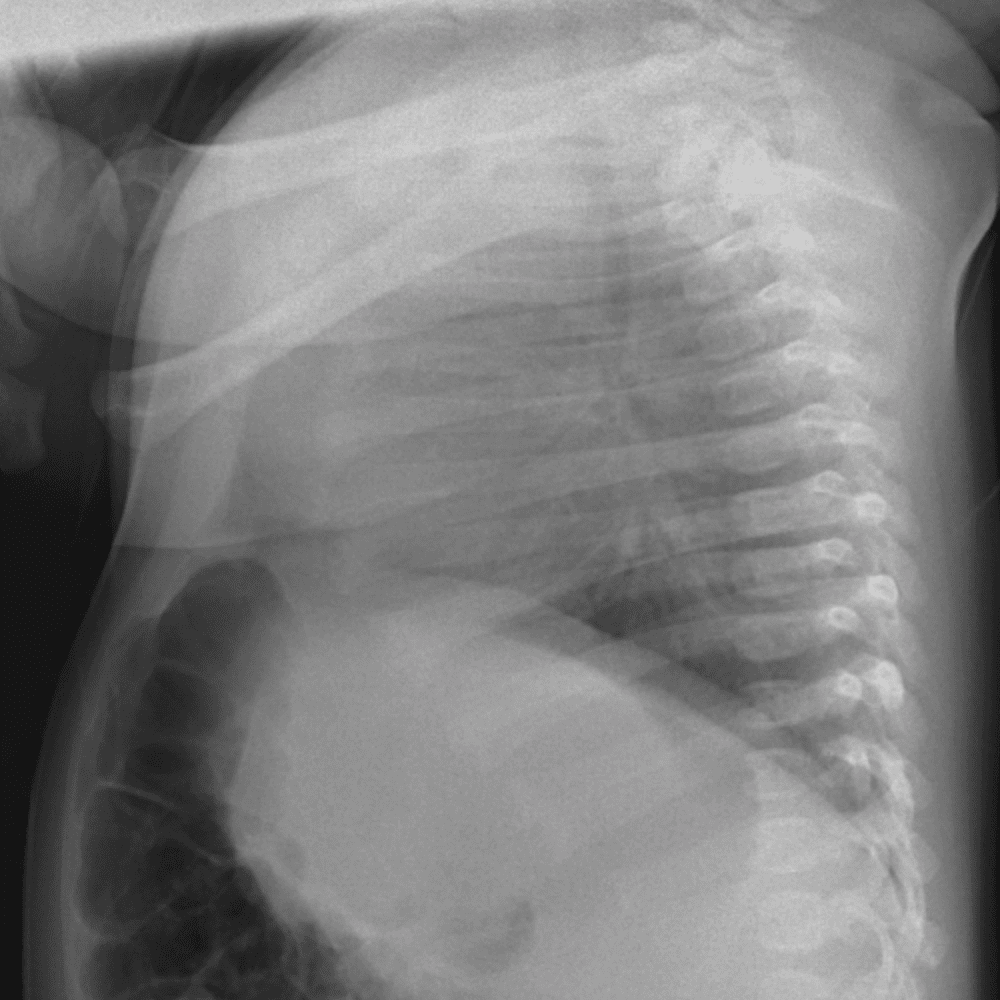

Peds Chest

Practice

Simulates call by including subtle or difficult cases and some normals.

50 cases